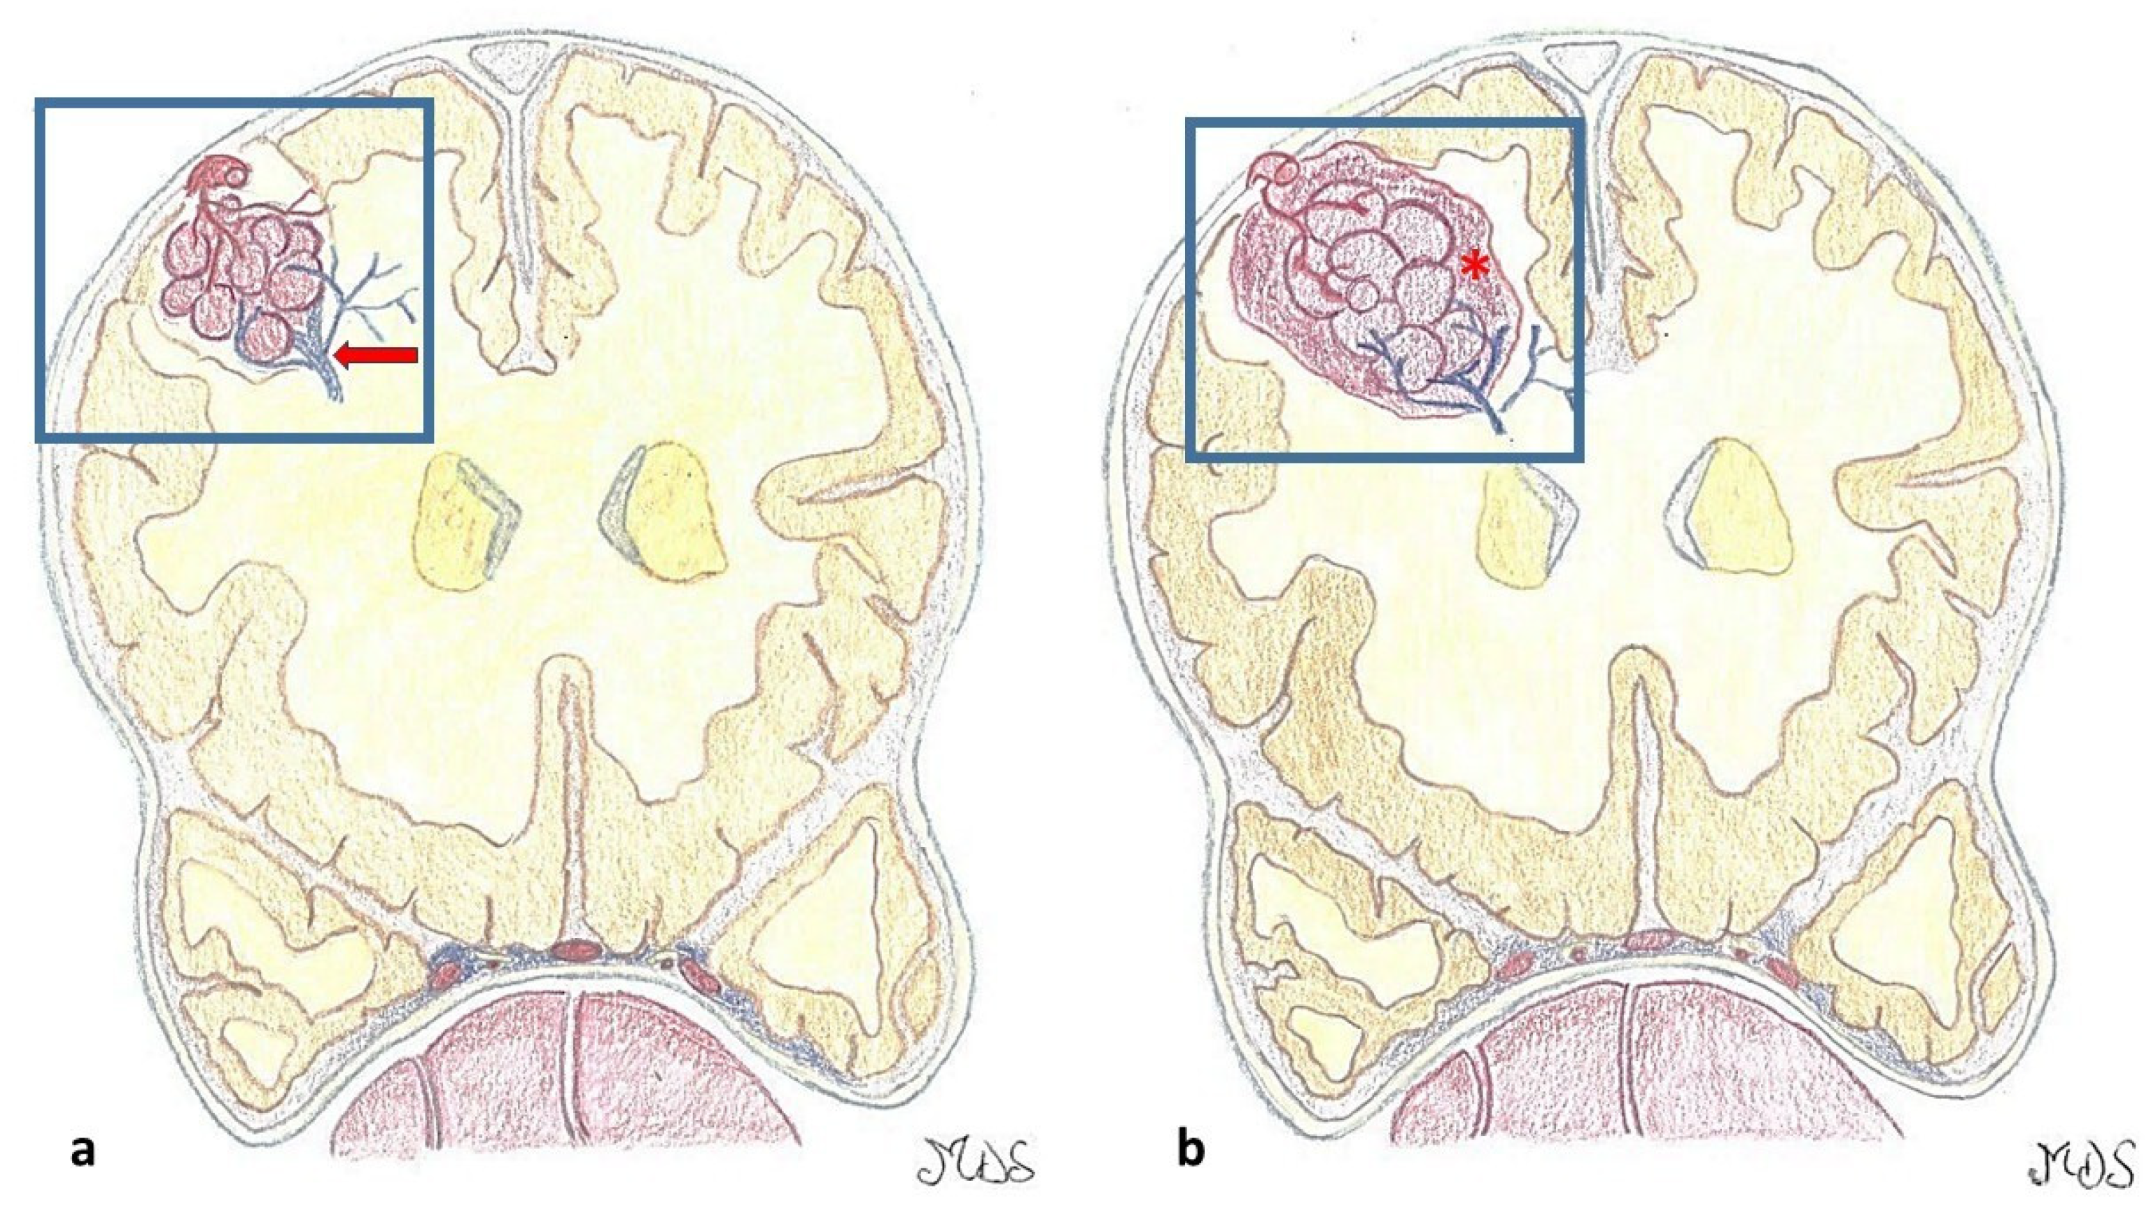

3.3. Cavernous Malformation and Epilepsy